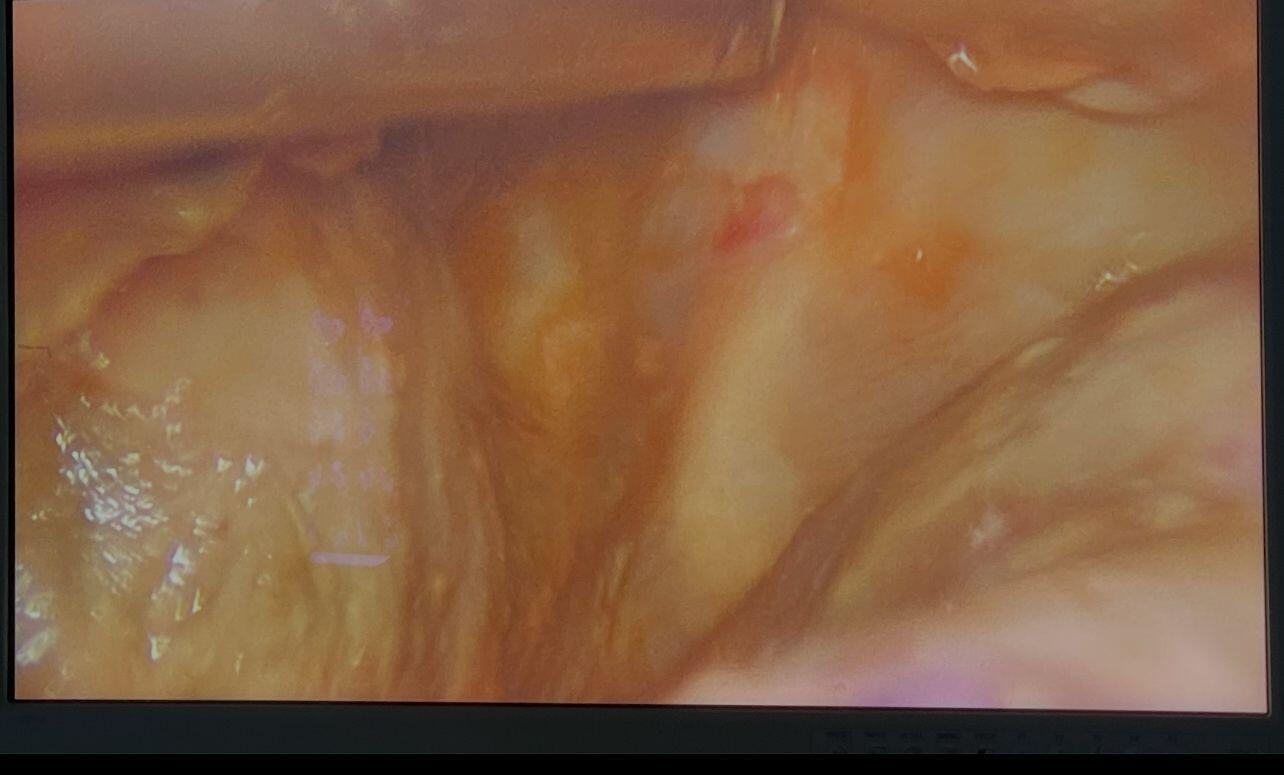

After 4 weeks of Albendazole, we performed Laparoscopic Hydatid cyst excision with lavage, drain placement, and Cholecystectomy.

1x10 mm and 3x5 mm ports were used for the surgery.